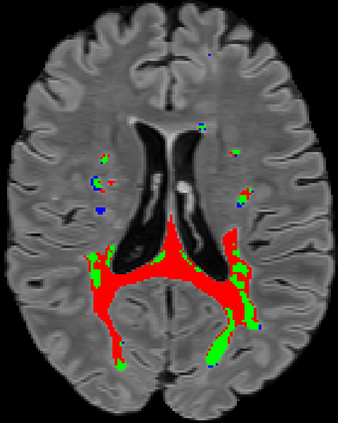

Recently, segmentation methods based on Convolutional Neural Networks (CNNs) showed promising performance in automatic Multiple Sclerosis (MS) lesions segmentation. These techniques have even outperformed human experts in controlled evaluation conditions such as Longitudinal MS Lesion Segmentation Challenge (ISBI Challenge). However state-of-the-art approaches trained to perform well on highly-controlled datasets fail to generalize on clinical data from unseen datasets. Instead of proposing another improvement of the segmentation accuracy, we propose a novel method robust to domain shift and performing well on unseen datasets, called DeepLesionBrain (DLB). This generalization property results from three main contributions. First, DLB is based on a large group of compact 3D CNNs. This spatially distributed strategy ensures a robust prediction despite the risk of generalization failure of some individual networks. Second, DLB includes a new image quality data augmentation to reduce dependency to training data specificity (e.g., acquisition protocol). Finally, to learn a more generalizable representation of MS lesions, we propose a hierarchical specialization learning (HSL). HSL is performed by pre-training a generic network over the whole brain, before using its weights as initialization to locally specialized networks. By this end, DLB learns both generic features extracted at global image level and specific features extracted at local image level. DLB generalization was validated in cross-dataset experiments on MSSEG'16, ISBI challenge, and in-house datasets. During experiments, DLB showed higher segmentation accuracy, better segmentation consistency and greater generalization performance compared to state-of-the-art methods. Therefore, DLB offers a robust framework well-suited for clinical practice.